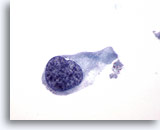

画像 1

肺FNA、単純ヘルペスウイルス肺感染症

多核化、核の相互圧排、スリガラス様クロマチンのほか、好酸性の核内封入体などウイルス性細胞変性に特徴的な様相が認められます。

60倍

画像 1

肺FNA、単純ヘルペスウイルス肺感染症

多核化、核の相互圧排、スリガラス様クロマチンのほか、好酸性の核内封入体などウイルス性細胞変性に特徴的な様相が認められます。

60倍